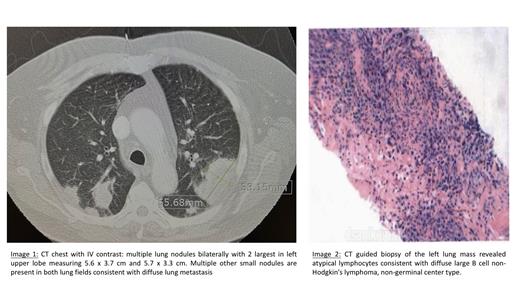

CT guided biopsy of the left lung mass surprisingly revealed diffuse large B cell non-Hodgkin's lymphoma, non-germinal center type. (Image 1) Immuno-histochemistry showed atypical lymphocytes positively stained with CD20, BCL6, BCL2, PAX5 and MUM1. C-myc had 50% positivity. Ki67 had 90% proliferative index. FISH analysis was negative for MYC, BCL2 and BCL6; hence there was no double hit lymphoma detected.